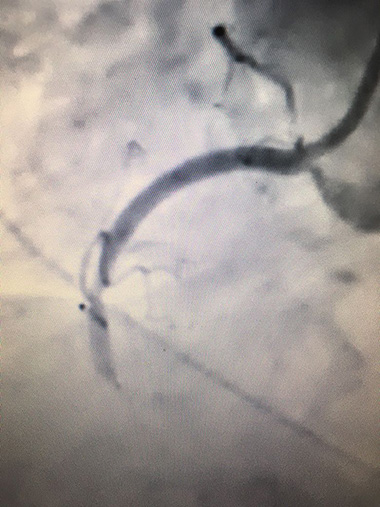

Invasive coronary angiogram showing a blocked right coronary artery

Treatment usually starts with targeting and controlling known cardiac risk factors such as smoking, diabetes, high blood pressure, elevated cholesterol, and achieving lifestyle modification with diet and exercise. Patients with angina often require anti-anginal medication such as beta blockers, an emergency GTN spray, blood thinners such Aspirin, and cholesterol lowering medication such as a statin to control symptoms and reduce the risk of heart attack, known as myocardial infarction. Patients with high risk features may require invasive procedures including coronary angiography sometimes proceeding immediately to angioplasty with stent insertion or referral for cardiac bypass surgery.